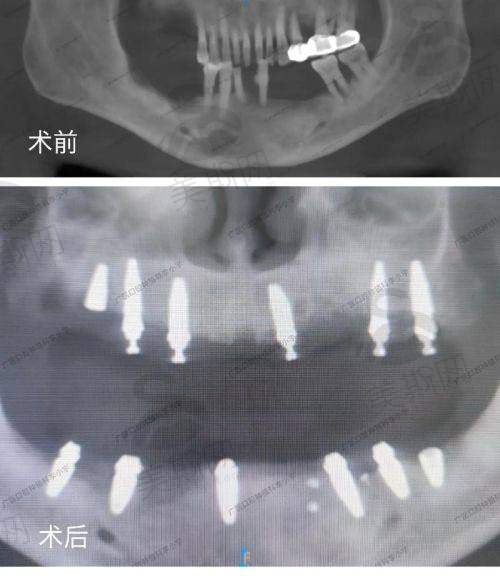

数字化精细种植牙:采用3D导板导航技术,实现种植体精细植入,适配单颗、多颗、半口/全口缺失修复,支持即刻种植、即刻负重,术后当天即可进食,适合高龄及骨条件差的患者。

数字化精细种植体系:该技术整合“3D口腔CT扫描、计算机辅助设计(CAD)、3D导板打印、微创种植”四大环节,术前通过CT获取牙槽骨密度、高度、宽度等数据,在计算机上模拟种植体角度、深度及咬合关系,生成个性化导板;术中医生无需翻瓣,通过导板精细植入种植体,手术时间缩短至30分钟/颗,创伤面积减少60%,术后肿胀轻、修复快,适用于骨量不足患者(结合自体骨移植或骨粉填充技术),复杂病例修复成功几率达98.7%。该技术已获国内专项认证,并被中华口腔医学会列为“种植技术推广项目”。